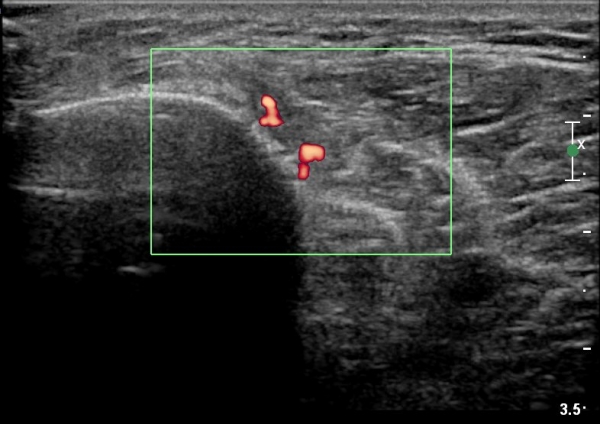

[¹«¸­] °æ°ñ ÇǷΰñÀý ÃÊÀ½ÆÄ¼Ò°ß(sonographic findings of stress fracture of tibia)

¿ìÃø ¹ß¸ñ°ú ¾Æ·§´Ù¸® ÅëÁõ(±â°£ 2ÁÖ)

±º´ë¿¡ ÀÔ´ëÇÏ¿© ÈÆ·ÃÀ» ¹ÞÀº º´·ÂÀÌ Àִ ȯÀÚ´Â ¾à 2ÁÖ ÀüºÎÅÍ ¹ß¸ñ ºÎÀ§ÀÇ ÅëÁõÀÌ ÀÖ´ø Áß

ÃÖ±Ù¿¡´Â ¹ß¸ñ À§ ¾Æ·§´Ù¸®¿¡ ÅëÁõÀÌ ¹ß»ýÇÏ°í ½ÉÇÏ°Ô °ÉÀ¸¸é ½ÉÇØÁö´Â ¾ç»óÀÓ

¾Æ·§´Ù¸® Áß°£ ºÎÀ§¿¡ °æ¹ÌÇÑ ¿¬ºÎÁ¶Á÷ ºÎÁ¾ÀÌ °üÂûµÇ°í ¾à°£ÀÇ ±¹¼ÒÀû ¾ÐÅëÀ» º¸ÀÓ.

ÃÊÀ½ÆÄ °Ë»ç

¹Ì¼¼ÇÏ°Ô ¿¬ºÎÁ¶Á÷ ºÎÁ¾°ú °¡°ñ Çü¼ºÀÌ °üÂûµÊ.

Bilateral stress fracture of the tibia diagnosed by ultrasound. A case report

https://www.ncbi.nlm.nih.gov/pmc/articles/PMC3558228/pdf/main.pdf